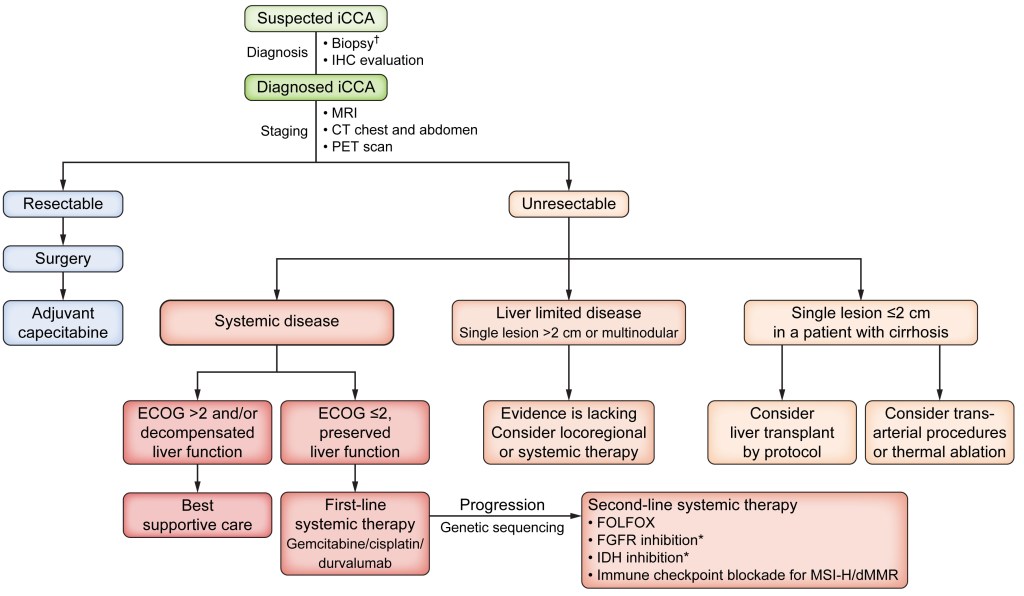

COLANGIOCARCINOMA

O colangiocarcinoma é o câncer derivado das células biliares, tanto no interior quanto no exterior do fígado (vesícula e ductos biliares), sendo o segundo câncer primário mais comum do fígado. Surge principalmente em homens (3 homens para cada mulher), geralmente entre os 70 e 80 anos com uma incidência dessa doença é de 2 a 2,8 casos a cada 100.000 pessoas.

Na maioria das vezes o colangiocarcinoma é esporádico, ou seja, sem uma causa clara. As pessoas de maior risco são aquelas portadoras de parasitas das vias biliares (raros no Brasil), colangite esclerosante primária (outra doença que pode levar à cirrose), colite ulcerativa (doença que leva a diarreia crônica, com episódios de sangramento, em adultos jovens), cálculos biliares, doença de Caroli e cistos de colédoco (tipos I e IV).

Esse tipo de câncer cresce silenciosamente nos canais biliares até que estes sejam obstruídos, levando aos sintomas de icterícia, fezes claras e urina escura, além de perda do apetite e emagrecimento. Ocasionalmente, pode ser descoberto em exames de rotina ou durante o acompanhamento de pacientes com colangite esclerosante primária.

Exames laboratoriais são pouco úteis nessa doença, podendo haver aumento em CA 19-9 e CA 125, mas eles podem também estar aumentadas em outras doenças e normais mesmo no colangiocarcinoma. O exame laboratorial de dosagem de IgG4 pode ser útil para diferenciar o colangiocarcinoma da colangiopatia associada à imunoglobulina 4, uma condição recentemente descoberta, que pode parecer câncer e que responde a imunossupressão.

O diagnóstico geralmente é realizado por exames de imagem, sendo a ressonância nuclear magnética o exame de escolha, particularmente a colangiorressonância (RNM realizada com foco no estudo das vias biliares). A colangiopancreatografia retrógrada endoscópica (CPRE) pode ser realizada quando for necessário colher material para biópsias ou para a colocação de próteses para desobstruir e manter as vias biliares abertas.

A ecoendoscopia ou ultrassonografia endoscópica permite também avaliar a lesão e realizar biópsias por punção, quando não há obstrução e houver a preocupação da CPRE causar infecção no fígado ou pâncreas. Por outro lado, existe o risco da punção da ecoendoscopia espalhar o tumor. Recentemente, surgiu a possibilidade da endoscopia das vias biliares, com aparelhos de endoscopia tão finos que podem entrar nos canais da bile e colher biópsias direto das lesões, com precisão diagnóstica muito maior.

Atualmente, o único grupo de pacientes com indicação de exame radiológico (não invasivo) de rastreamento do colangiocarcinoma é o de portadores de colangite esclerosante primária, pois esses tem um risco de 20% de desenvolver esse tipo de câncer ao longo da vida. Não está bem claro qual o melhor método de rastreamento, mas a recomendação atual da sociedade européia (EASL) é de ressonância com colangiorressonância anualmente. Se o paciente está em fase de cirrose, o rastreamento é o mesmo que para o hepatocarcinoma, com ultrassom semestral.

Não há, até o momento, nenhuma recomendação clara sobre quem deve fazer exames periódicos para detectar o colangiocarcinoma no início, nem que exames devem ser realizados. Qualquer esquema de rastreamento tem que levar em conta não só o custo financeiro, mas também as complicações e o risco de falsos positivos, e nenhum esquema até agora parece adequado. Sabemos que portadores de colangite esclerosante primária e pólipos de vesícula biliar têm maior risco, e que possivelmente a colangiorressonância periódica possa ser benéfica nos portadores da CEP. Já nos pólipos de vesícula biliar, o mais recomendado seria operar os portadores de pólipos maiores de 10mm ou que estejam crescendo e evitar o surgimento do câncer.

Infelizmente, o diagnóstico ainda é feito tardiamente, já que a maioria dos pacientes não têm fatores de risco claros e os sintomas surgem com a doença mais avançada. O tratamento ideal é a cirurgia, mas ela só é realizável em menos de um terço dos pacientes. É uma cirurgia grande, de risco, mas com possibilidade de cura quando possível, especialmente quando associada a quimio ou radioterapia. Quando não é possível, medidas paliativas como as descritas para o hepatocarcinoma podem ser empregadas. O transplante hepático só é realizado em casos muito selecionados pelo alto risco de recidiva após o transplante.